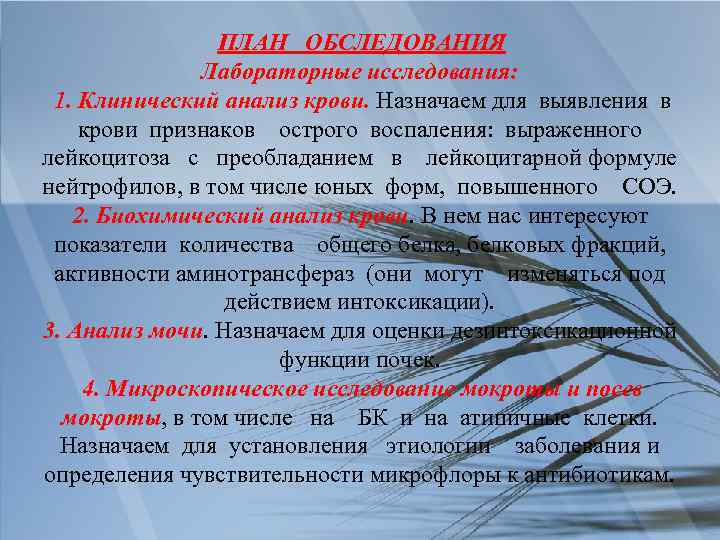

ПЛАН ОБСЛЕДОВАНИЯ Лабораторные исследования: 1. Клинический анализ крови. Назначаем для выявления в крови признаков острого воспаления: выраженного лейкоцитоза с преобладанием в лейкоцитарной формуле нейтрофилов, в том числе юных форм, повышенного СОЭ. 2. Биохимический анализ крови. В нем нас интересуют показатели количества общего белка, белковых фракций, активности аминотрансфераз (они могут изменяться под действием интоксикации). 3. Анализ мочи. Назначаем для оценки дезинтоксикационной функции почек. 4. Микроскопическое исследование мокроты и посев мокроты, в том числе на БК и на атипичные клетки. Назначаем для установления этиологии заболевания и определения чувствительности микрофлоры к антибиотикам.